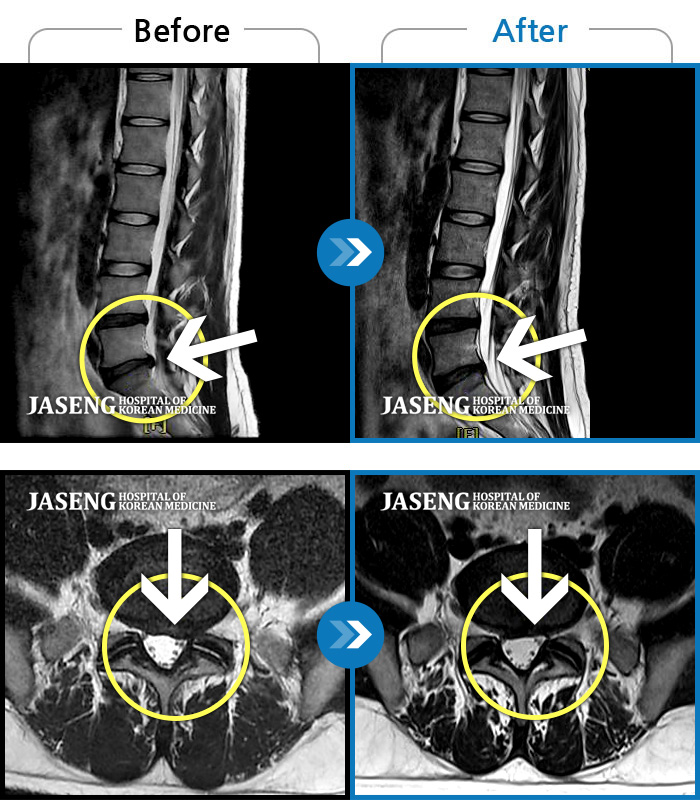

MRI 치료사례

양측 허리 통증과 좌측 허벅지부터 발바닥까지 송곳으로 찌르는 듯한 통증 지속되어 내원하셨습니다.